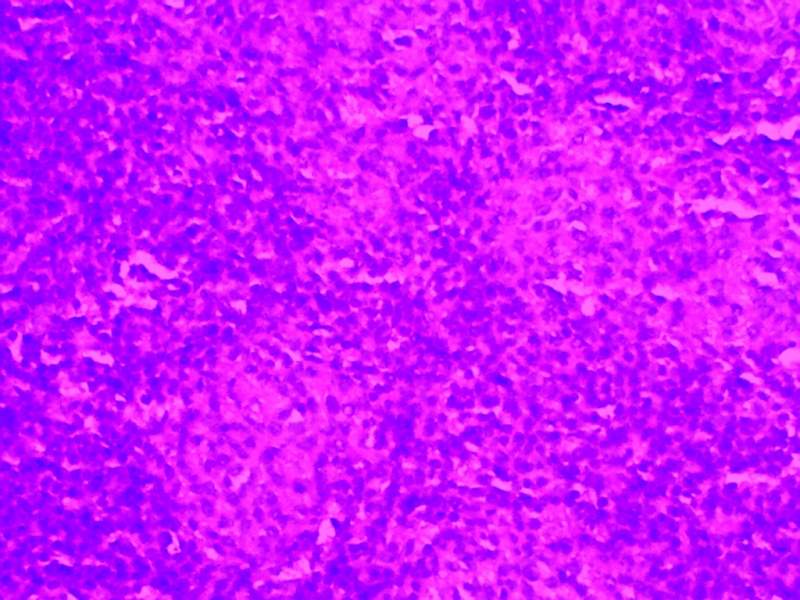

³û¼¦Æ¢ÔàHEȾɫ½á¹û·ÖÎö

ÎÒ×öµÄÊdzû¼¦Æ¢ÔàµÄHEȾɫ£¬Õý³£×éºÍÓв¡×éµÄ 21Óв¡×é-01.jpg 21Óв¡×é-03.jpg 21Õý³£×é+01.jpg 35Óв¡×é-01.jpg 35Õý³£×é+02.jpg |